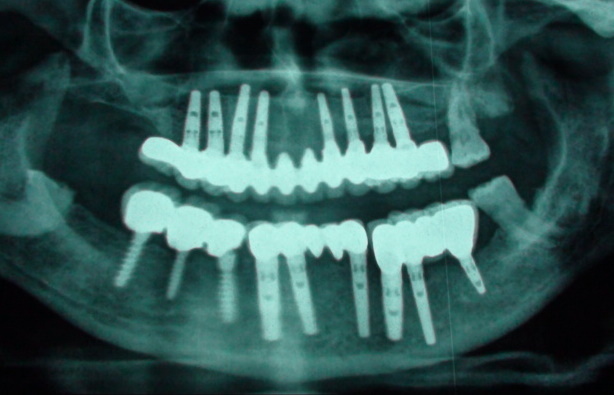

Read moreIn the past decade, Dental Implant has gained a very high popularity and is now the preferred method for replacement of single to multiple teeth. Although during the introduction of dental implant t…